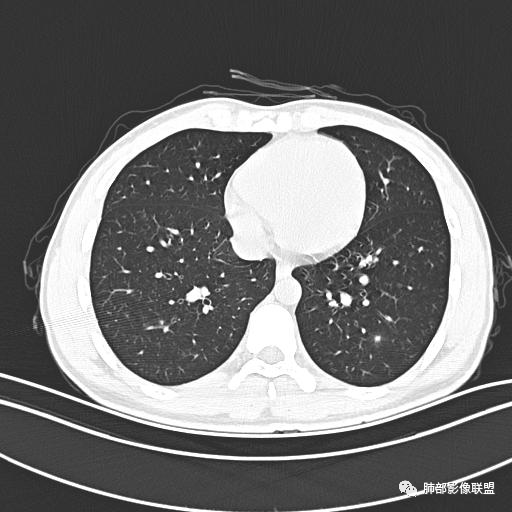

小强:青年,发热,皮疹;双肺散在结节,周围磨玻璃,点晕征,疱疹病毒感染,鉴别荚膜组织胞浆菌,结核。 大雄:青年,急性起病,发热伴全身皮疹2天,抗病毒治疗体温有下降。双肺随机分布大小不等类圆结节,“点晕征”。考虑水痘-疱疹病毒(VZV)血播询问接触史,查体皮疹分布以及形态基本可诊断。 王开金江津中心医院呼吸科:青年男性,起病急,病程短,以发热,皮疹为首发症状,感染指标以单核细胞升高为主,胸部ct双肺多发结界,周围有晕,点晕表现,随机分布,同意於老师意见,水痘疱疹病毒血流感染累及肺。 王秀仙:双肺多发大小不等结节,周围有晕,边缘模糊,呈点晕征表现。青年,急性起病,发热伴全身皮疹2天,抗病毒治疗体温有下降。考虑疱疹病毒。鉴别荚膜组织胞浆菌。 傅昌瑜:19岁男性,发热、全身皮疹2天,单核细胞增高,双肺多发结节,结节边缘见边界不清磨玻璃影。点晕征+发热、全身皮疹+单核细胞增高——考虑水痘-带状疱疹病毒肺炎。 一切∮随缘:年轻男性,发热,皮疹两天,实验室,CRP,PCT增高,影像:双肺多发散在磨玻璃结节,边界欠清,大小不等,呈点晕征改变,以血管束周围分布为主,局部血管束略增粗,其它无明显改变,考虑:1:病毒性肺炎(水痘疱疹病毒?不知道皮肤有无改变)2:真菌(组织胞浆菌,血管侵袭性肺曲霉)3:GPA4:寄生虫(实验室没有看到嗜酸细胞增高) 赵山河:双肺散在结节,周围有晕,边缘模糊,呈点晕征表现。青年,急性起病,发热伴全身皮疹2天,抗病毒治疗体温有下降。考虑水痘—疱疹病毒感染。洪桥爱:青年男性,发热、皮疹2天,伴瘙痒,皮疹于面部首发,之后进展至全身,虽然没有对皮疹进行描述,但是从出疹时间及皮疹进展情况,伴瘙痒,应该就是个水痘患者;CT提示双肺随机分布结节影,部分结节伴有边界不清晕征,考虑水痘血播肺。 刘强:年轻男性,急性起病,皮疹,发热,抗感染治疗体温下降,说明有效。影像表现为散在点晕征,感染类疾病谱(疱疹病毒,真菌,结核),结合年龄,皮肤皮疹,考虑水痘-疱疹病毒性肺炎。 小兜:男性,19岁,发热皮疹两天,颜面部至全身,CRP,降钙素及单核增高。CT示双肺散在小结节,周围伴磨玻璃影,点晕征,考虑为水痘-带状疱疹病毒(varicella-zoster virus,VZV)肺炎 必有路:青年,皮疹+发热+“点晕征”→水痘-疱疹病毒(VZV) 许慧良:青年男性患者,发热、皮疹2天,体温最高38.5℃,第3天皮疹扩展至全身,伴瘙痒,胸部CT:双肺多发随机分布的小结节,结节周边见边界模糊的晕征,考虑水痘病毒感染流心明智:男,19,急性起病,发热伴全身皮疹2天。出疹顺序头→全身,抗病毒有效。胸部CT:两肺多发大小不等类圆形实性小结节影,随机分布,结节周围环绕GGO,边界模糊,呈点晕征。出疹特点是关键,未提示。考虑:血播病毒性肺炎,水痘-疱疹病毒?麻疹?鉴别荚膜组织胞浆菌、TB、血管炎、寄生虫等。 浪迹天涯:病灶多为5-10mm大小结节,结节周围可见磨玻璃样的晕环,常多发,可分布于肺内任何区域,考虑水痘—带状疱疹病肺炎如果短时间内有新的一个区域浸润,更加能说明,